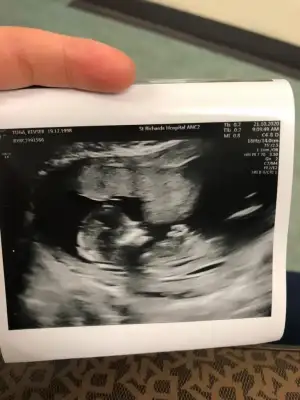

Ayy çok teşekkürler. vajinaldiii. Kalp atışı çok fazla olduğu için doktor da kız olabilir dedi. Hadi bakalım

Bu benım 7 haftalık kesem canım bakabilir mısın6 7 haftalık kesenin resmi varsa ona bakim bide bu büyük 12 13 haftalık resminide yollayın varsa

Bana da bir yorum yapar mısınız6 7 haftalık kesenin resmi varsa ona bakim bide bu büyük 12 13 haftalık resminide yollayın varsa

teşekkürler![]()